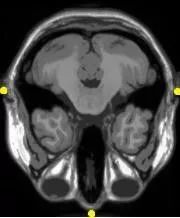

图像配准在医学图像处理与分析中有众多具有实用价值的应用。随着医学成像设备的进步,对于同一患者,可以采集含有准确解剖信息的图像诸如CT,MRI;同时,也可以采集到含有功能信息的图像诸如SPECT。然而,通过观察不同的图像进行诊断需要凭着空间想象和医生的主观经验。采用正确的图像配准方法则可以将多种多样的信息准确地融合到同一图像中,使医生更方便更精确地从各个角度观察病灶和结构。同时,通过对不同时刻采集的动态图像的配准,可以定量分析病灶和器官的变化情况,使得医疗诊断、制定手术计划、放射治疗计划更准确可靠。

多模配准常见于医学图像领域,故以多模医学图像配准为例。

由于医学成像设备可以提供关于患者不同信息不同形式的图像(计算机断层扫描CT,核磁共振MRI,正电子发射断层成像PET,功能核磁共振fMRI等)。

基于单种或多种模态图像的配准,可划分为单模态(Single-modality)和多模态(Multi-modality)。